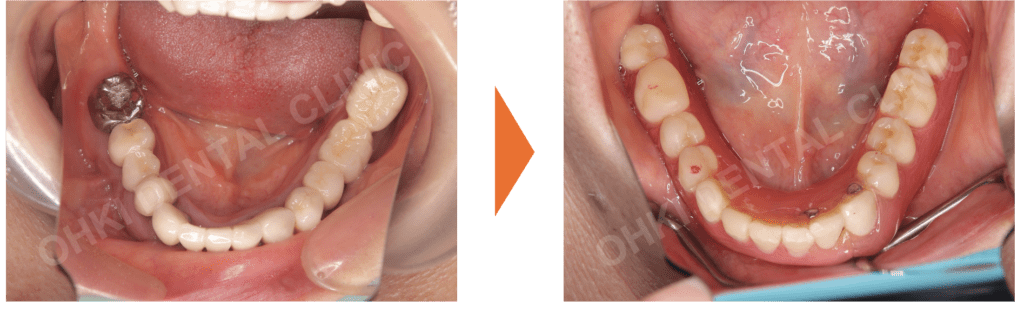

・重度の歯周病(Pタイプ)により、すでに多くの歯を失っている状態でした。

・不適合な補綴物(被せ物)が多数あり、残っている歯も歯周病で保存が難しいものが含まれていました。

・全体的に欠損が大きく、機能的な崩壊が見られる状態でした。

左上奥歯にはインプラントを埋入して垂直的な噛み合わせを支え、それ以外の部分はセラミックブリッジによる固定式での再建を選択しました。 - 下顎の再建:

インプラントも検討されましたが、まずは負担の少ないパーシャルデンチャー(部分入れ歯)を経由し、将来的にインプラントへ移行できる計画としました。

仕上がりの特徴

- スマイルラインが非常に綺麗に改善され、若々しい口元になりました。

- 前歯から奥歯までしっかり噛めるようになり、機能的な回復を遂げました。

- 初診時と比べ、咬合平面(噛み合わせのライン)が整い、痛みや違和感なく食事ができるようになりました。